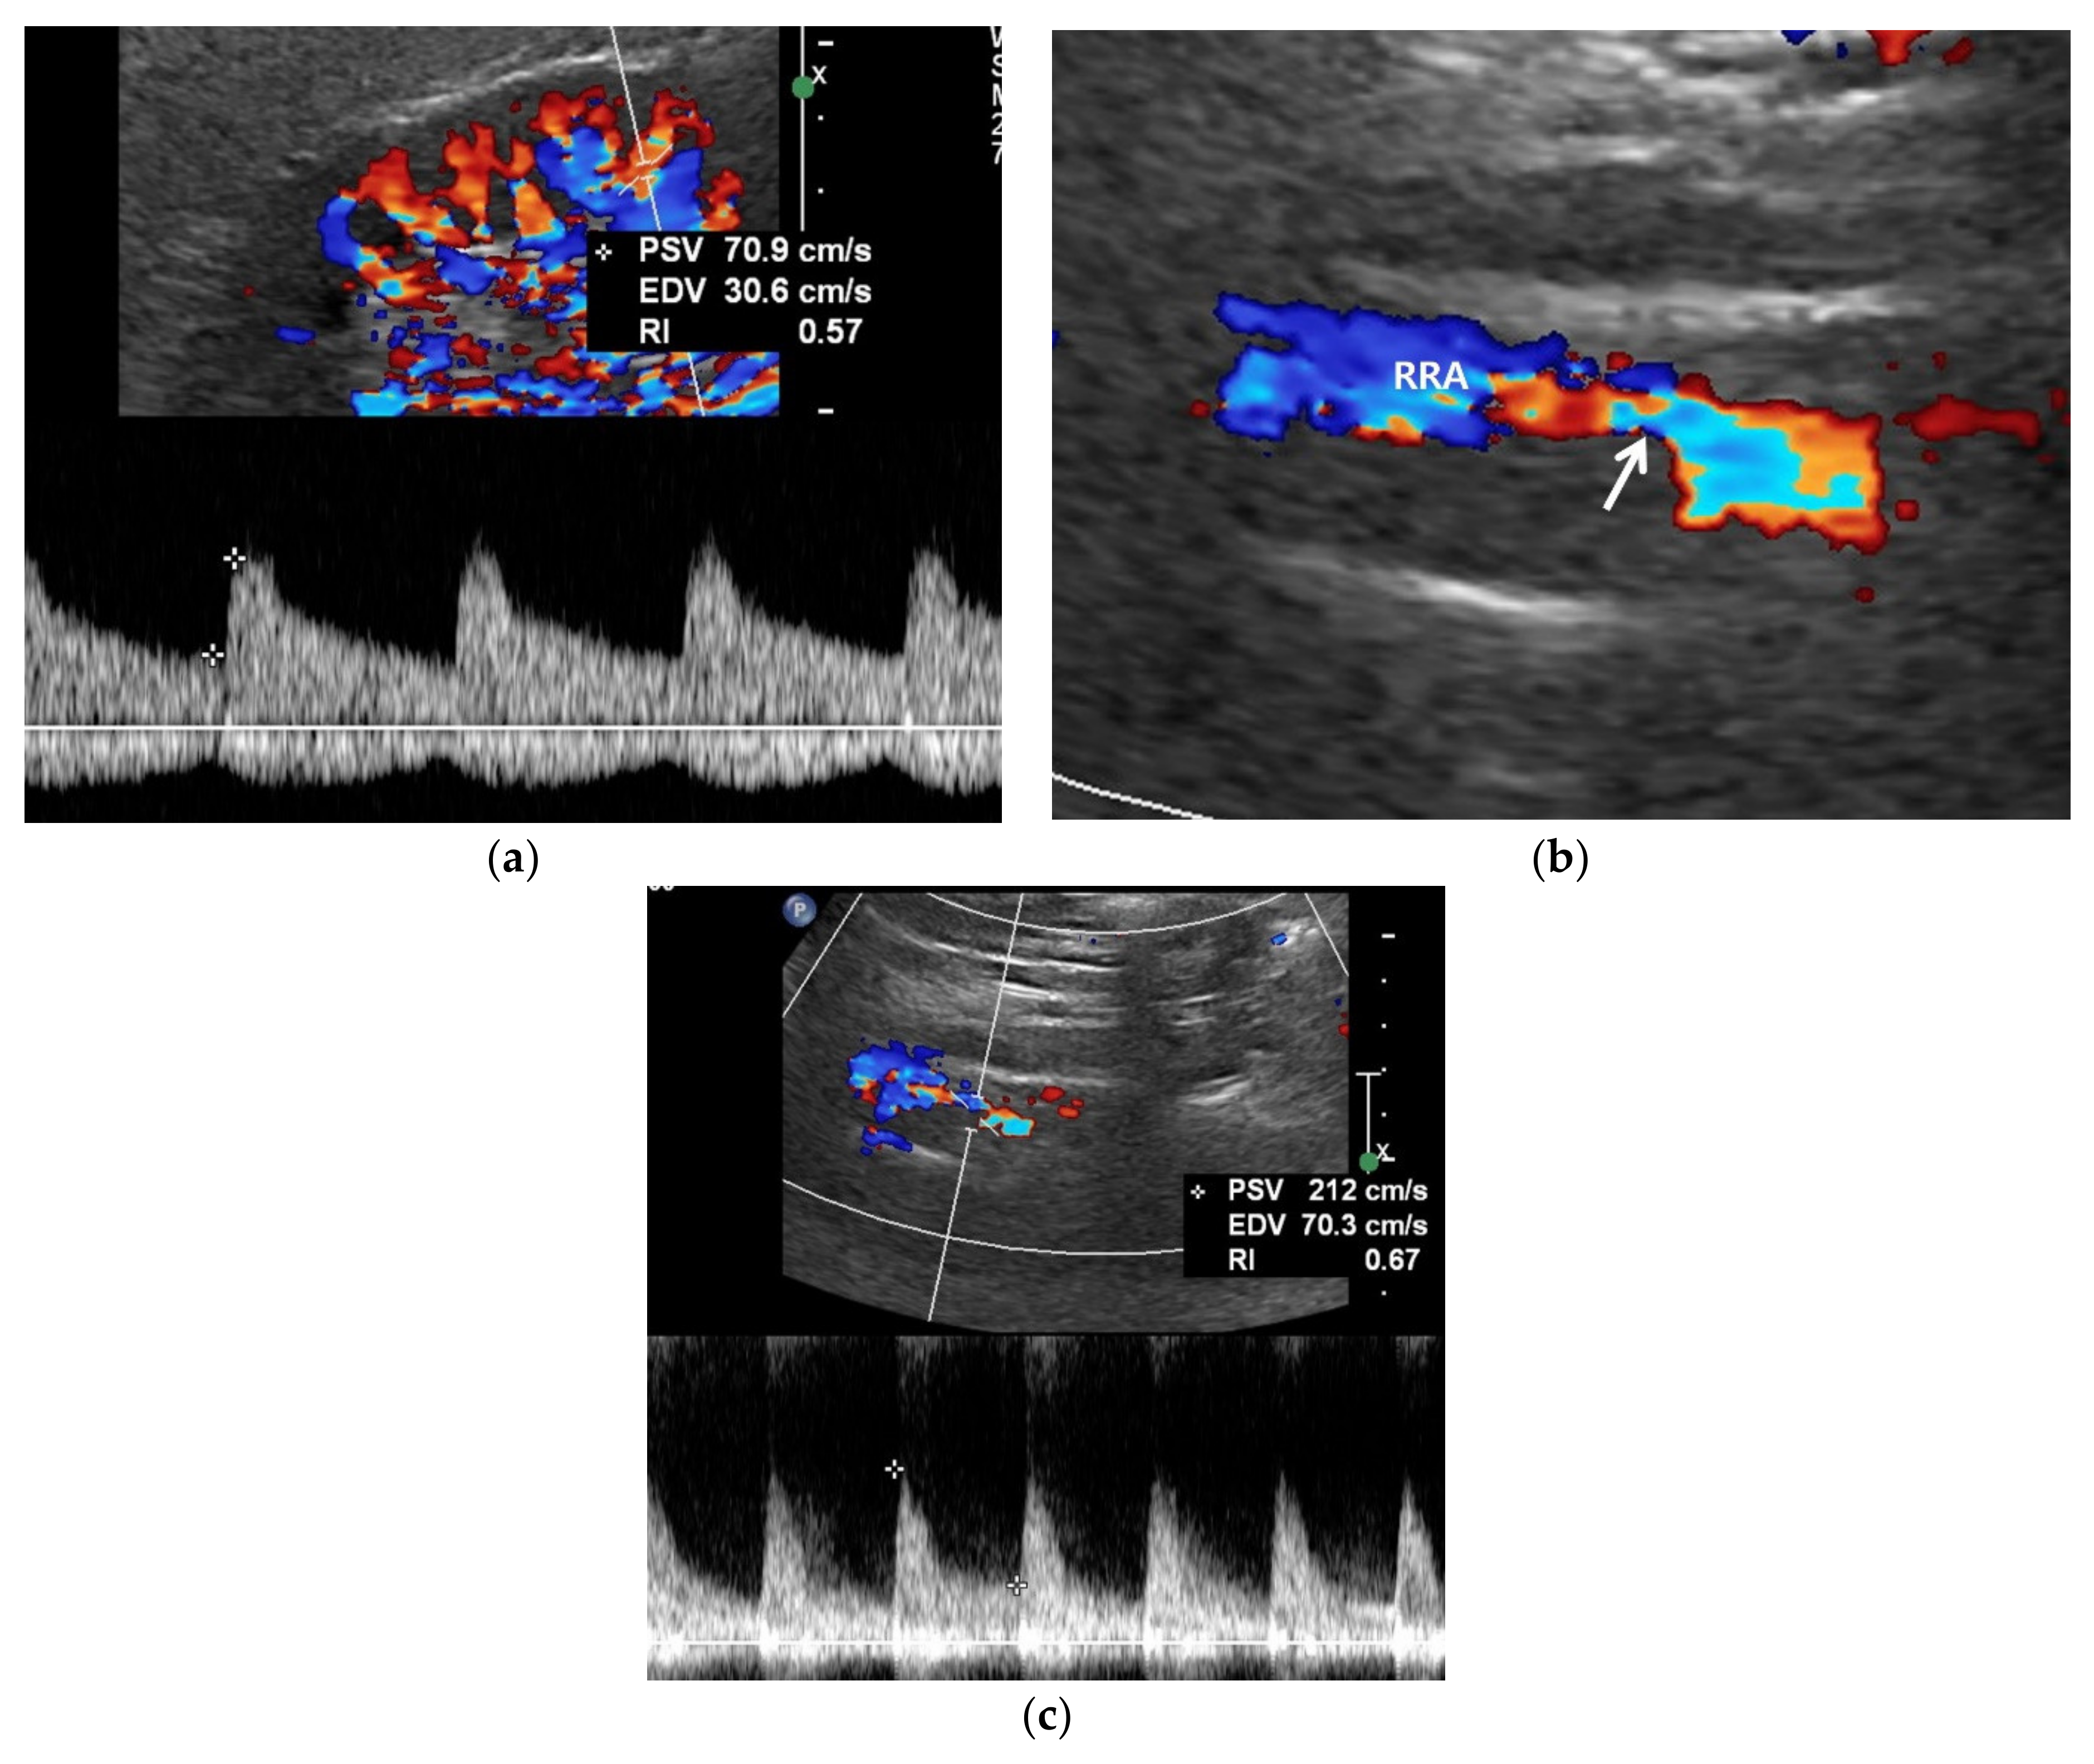

Figure 3.

RAS-positive renal artery US in a 20-year-old man with negative renal US. (a) Spectral Doppler US does not show pulsus tardus and parvus pattern in the right kidney even though the size (11 cm) and echogenicity appear normal. (b) Color Doppler US shows a focal stenosis (arrow) in the proximal right renal artery (RRA), suggesting RAS. (c) Spectral Doppler US shows a high peak systolic velocity (PSV) (212 cm/s) in the stenotic right renal artery.

Color Doppler US of the kidneys is not an ideal approach for detecting RAS. Renal perfusion can be normal in early stage RAS (Figure 4) and decreases in intermediate or late-stage RAS. Renal perfusion is an indirect finding suggesting RAS. Accordingly, it is not adequately sensitive for detecting early stage RAS.

Spectral Doppler US quantitatively measures the velocity of blood flow in the stenotic renal artery (Table 4). The peak systolic velocity (PSV) within the stenotic renal artery is frequently more than 180–200 cm/s [4,22,23,24,25,48] (Figure 2 and Figure 3). If PSV is more than 180 cm/s, the sensitivity and specificity for RAS range from 85–97% and 72–98%, respectively [24,25,28,31]. In case of unilateral RAS, PSV is significantly different between the two renal arteries. At this point, two simple concepts should be kept in mind: first, the normal PSV values in normal renal arteries without stenosis (about 70–100 cm/s), and, second, angle correction is essential to obtain reproducible and accurate measurements of PSVs. If the PSV of the renal artery is ≥3.5-fold that of the aorta (renal-to-aorta ratio (RAR)), it can suggest RAS [26,27,29,49] (Figure 4). The PSV RAR is another good indicator for identifying RAS. If RAR is 3.5 or greater, the sensitivity and specificity ranges are 91–92% and 71–95%, respectively [26,27,29]. It is important to determine where PSV is measured within the aorta because it differs by region-of-interest location. First, radiologists or sonographers should find the origin of the superior mesenteric artery (SMA) during the sagittal US scan; then, the PSV region of interest should be 1–2 cm below the SMA because the renal arteries are located below the origin of the SMA.

The frequency shift from the stenotic artery is not easy to detect with spectral Doppler US as it tends to be small (Figure 2 and Figure 3). There are some technical tips in assessing RAS: First, the critical angle between the renal artery flow and US from transducer should be observed when a good spectrum of arterial flow is not obtained. The optimal critical angle should be kept at 30–60° for detecting a good frequency shift [48]. Second, the sample volume size should be higher than that of the RAS to oversample frequency shifts. The renal artery spectrum can be identified by means of evaluating the flow direction and spectral pattern from among the various spectra given by arteries and veins. Third, the PSV of the renal artery should be measured in the poststenotic dilatation when a good spectrum cannot be obtained in the stenosis (Figure 2 and Figure 3). If the PSV is more than 180–200 cm/s, it will be higher in the stenotic artery. If RAS is severe, the frequency shifts are too weak to directly detect from the stenotic artery [23,49].